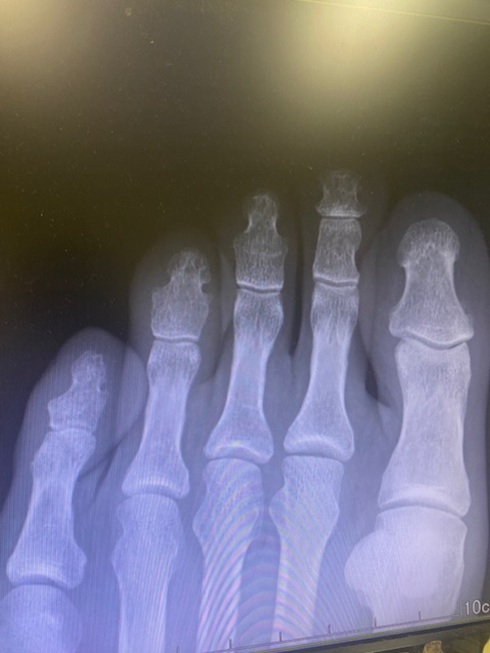

診断の結果、左足人差し指骨折と判明。どうりで痛いわけだといった感じですが、先ほどのナイチンゲールと違って医師はとても丁寧。レントゲン写真を指さしながら「ここに黒い線が見えるでしょ」とか、「指は全部で五本あるでしょ」とか、まるでチンパンジーになにか教えている感じとでも申しましょうか。とにかく医学用語を使わず、チンパンジーにもわかりやすいよう懇切丁寧に教えてくれたのでとても助かりました。

「あれ、関節ないですね」

どうやら聞くところによると本来足の指には三つの関節があるようなのですが、私は小指、人差し指、中指とすべて二つしかないとのことでこれは退化、簡単に言うとチンパンジー以下だということが判明致しまして…。どうりで丁寧に説明してくれたわけだと膝を打ったのですが、これを言うか言うまいか少しだけ迷いましたので、最後の一曲は「告白」ということにしておいてください。

※拡大すると分かりますが、左三本の指は関節がふたつしかありません。